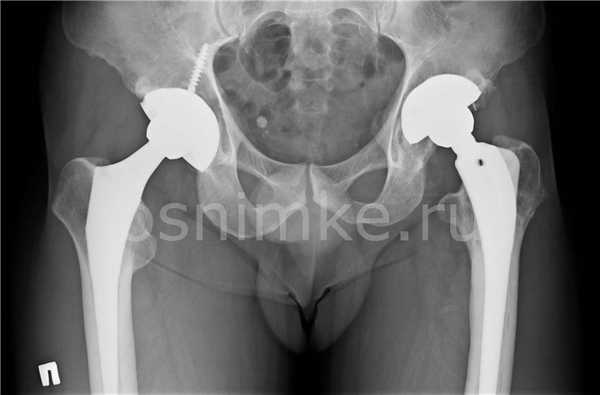

Эндопротезирование тазобедренного сустава

В начальных стадиях (1-2 стадии по Kellgren) ОА тазобедренных суставов при рентгенологическом исследовании определяются: незначительное сужение суставной щели, слабовыраженный субхондральный остеосклероз, точечные кальцификаты в области наружного края крыши вертлужной впадины (зачаток остеофитов), заострение краев ямки бедренной головки в области прикрепления круглой связки бедренной головки (рис. 1).

Рис. 1. Обзорная Rо-графия тазобедренного сустава в прямой проекции.

Деформирующий остеоартроз II ст. по Kollgren. Крупные остеофиты на краях суставных поверхностей. Грибовидная деформация бедренной головки